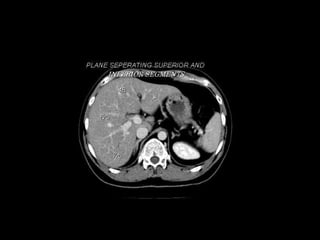

Radiographers use medical imaging equipment like X-rays and MRIs to produce images of patients' internal structures and organs. They are responsible for positioning patients, operating scanning machines, and ensuring quality images. Radiographers must have strong attention to detail, excellent communication skills, and the ability to work well under pressure to accurately capture anatomical features and diagnose any abnormalities.